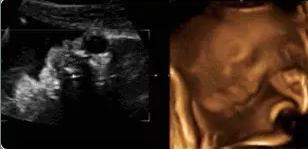

“四维彩超”——超声影像对于优生极其关键,可不少宝妈会遇到一种尴尬的情况,也让医生很头疼,那便是胎宝宝老趴着,基本上看不到五官及表情。

【在妇产科医院,你可以看到这样的胎宝】

本宝宝有些困了——打哈欠

麻麻,我正在挠耳朵

麻麻,我在咬手指哟!

霍霍,打拳啦~

本宝宝有些乏了——揉眼睛